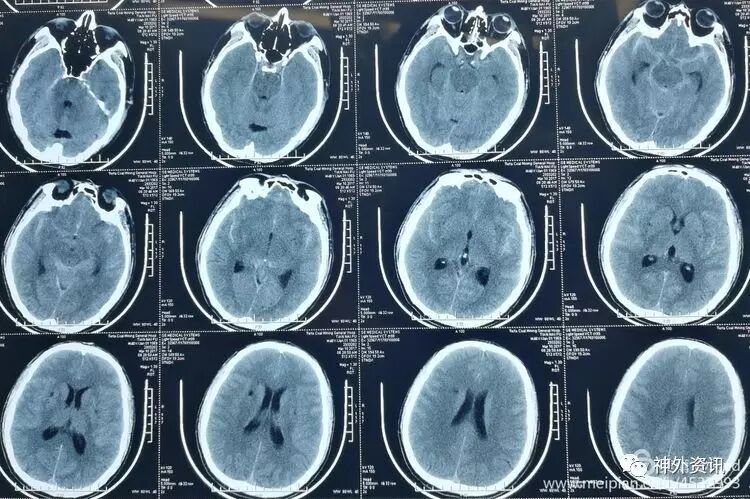

术后复查头CT显示手术效果满意。